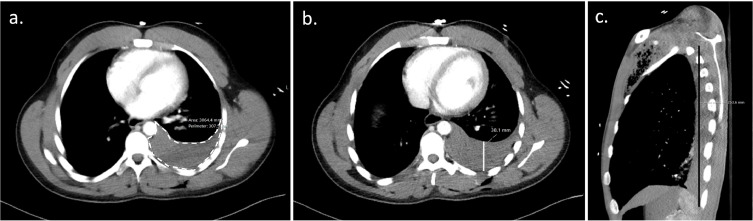

Over 300 ml of blood on a chest CT in a traumatically injured patient requires a tube thoracostomy. How do you calculate 300 ml of blood on a chest CT?

You use Mergo's formula.

Image B the AP line is what would represent d